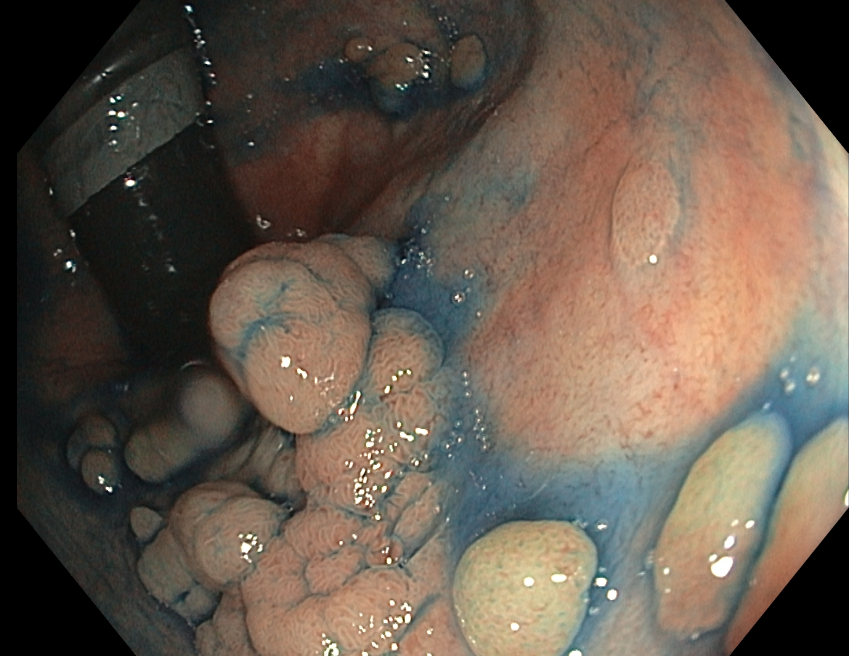

ENDOSCOPIE D'UN RECTUM NON CONSERVABLE

La conservation du rectum n’est pas envisageable en cas d’atteinte diffuse avec tapis d’adénomes confluents non accessibles à un traitement endoscopique itératif. La discussion doit être multidisciplinaire avec le chirurgien et endoscopiste interventionnel idéalement aidé par photos, vidéos et au besoin en RCP.